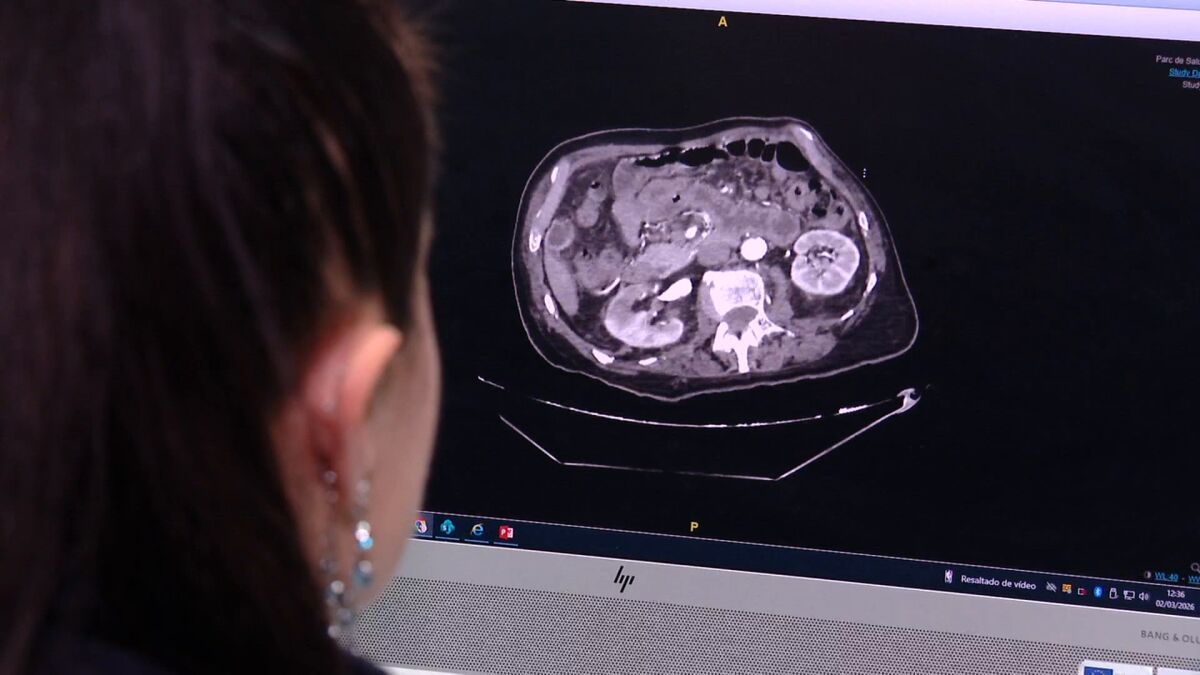

Según explica la doctora y cirujana del Hospital del Mar, Ana María González, se manifiesta con un fuerte dolor abdominal y la única forma de diagnosticar la enfermedad es a través de un TAC.

Ahora, con este nuevo protocolo se ha invertido el orden de las pruebas para conseguir un diagnóstico precoz. Es pionero en España y en el sur de Europa y se desarrolla, por el momento, únicamente en el hospital del Mar, en Barcelona. Ahora, cuando un paciente llega a urgencias y hay sospecha de que puede sufrir isquemia mesentérica aguda, se activa directamente este código y se le realiza la prueba TAC. Con ello se consigue un rápido diagnóstico que, en caso de confirmar la enfermedad, permite proporcionar un tratamiento precoz y reducir así la mortalidad.